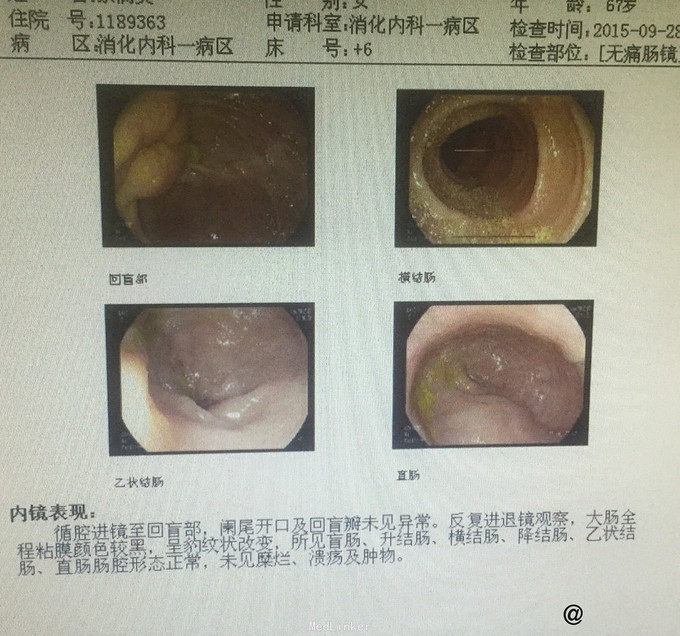

入院后完善相关检查 血常规:白细胞计数 13.84 ↑ 4~10 10^9/L。尿液分析及尿沉渣:白细胞 +- 阴性隐血 +- 阴性蛋白质 1+ 阴性糖 4+ 阴性,酮体 2+ 阴性。 生化全套2:白蛋白 32.9 ↓ 35~55 g/L球蛋白 39.9 ↑ 20~35 g/L白球比值 0.82 ↓ 1~2.5葡萄糖 20.85 ↑ 3.82~6.1 mmol。血脂肪酶及淀粉酶正常。红细胞沉降率 53 0~20 mm/h。糖化血红蛋白 11.7 ↑ <6 % 肿瘤全套2:癌胚抗原 405.13 ↑ 0~5 ng/ml,糖类抗原19-9 >1200.00 ↑ 0~37 U/mL。 头颅CT平扫未见明显异常。 胸部+上腹部CT提示:1.胃积气扩张,余上腹部CT平扫未见明显异常。2.肺气肿,支气管炎肺部表现;3.双肺间质性肺炎;4.主动脉硬化;5.主动脉窦致密影,考虑瓣膜钙化。 胰腺增强:1 胰腺CT增强未见明显异常。2 右肾小囊肿。 肠镜检查:大肠黑变病。胃镜检查:浅表性胃炎(2级)。 复查癌胚抗原 383.42 ↑ 0~5 ng/ml糖类抗原19-9 >1200.00 ↑ 0~37 U/mL,仍旧显著升高,为进一步排除肿瘤行病变,遂行盆腔磁共振检查:1.盆腔右侧占位,肿瘤性病变不除外,建议增强扫描。2.右侧附件区结节影,建议增强扫描。3.子宫肌层信号欠均匀,不除外腺肌病可能。4.盆腔少许积液。